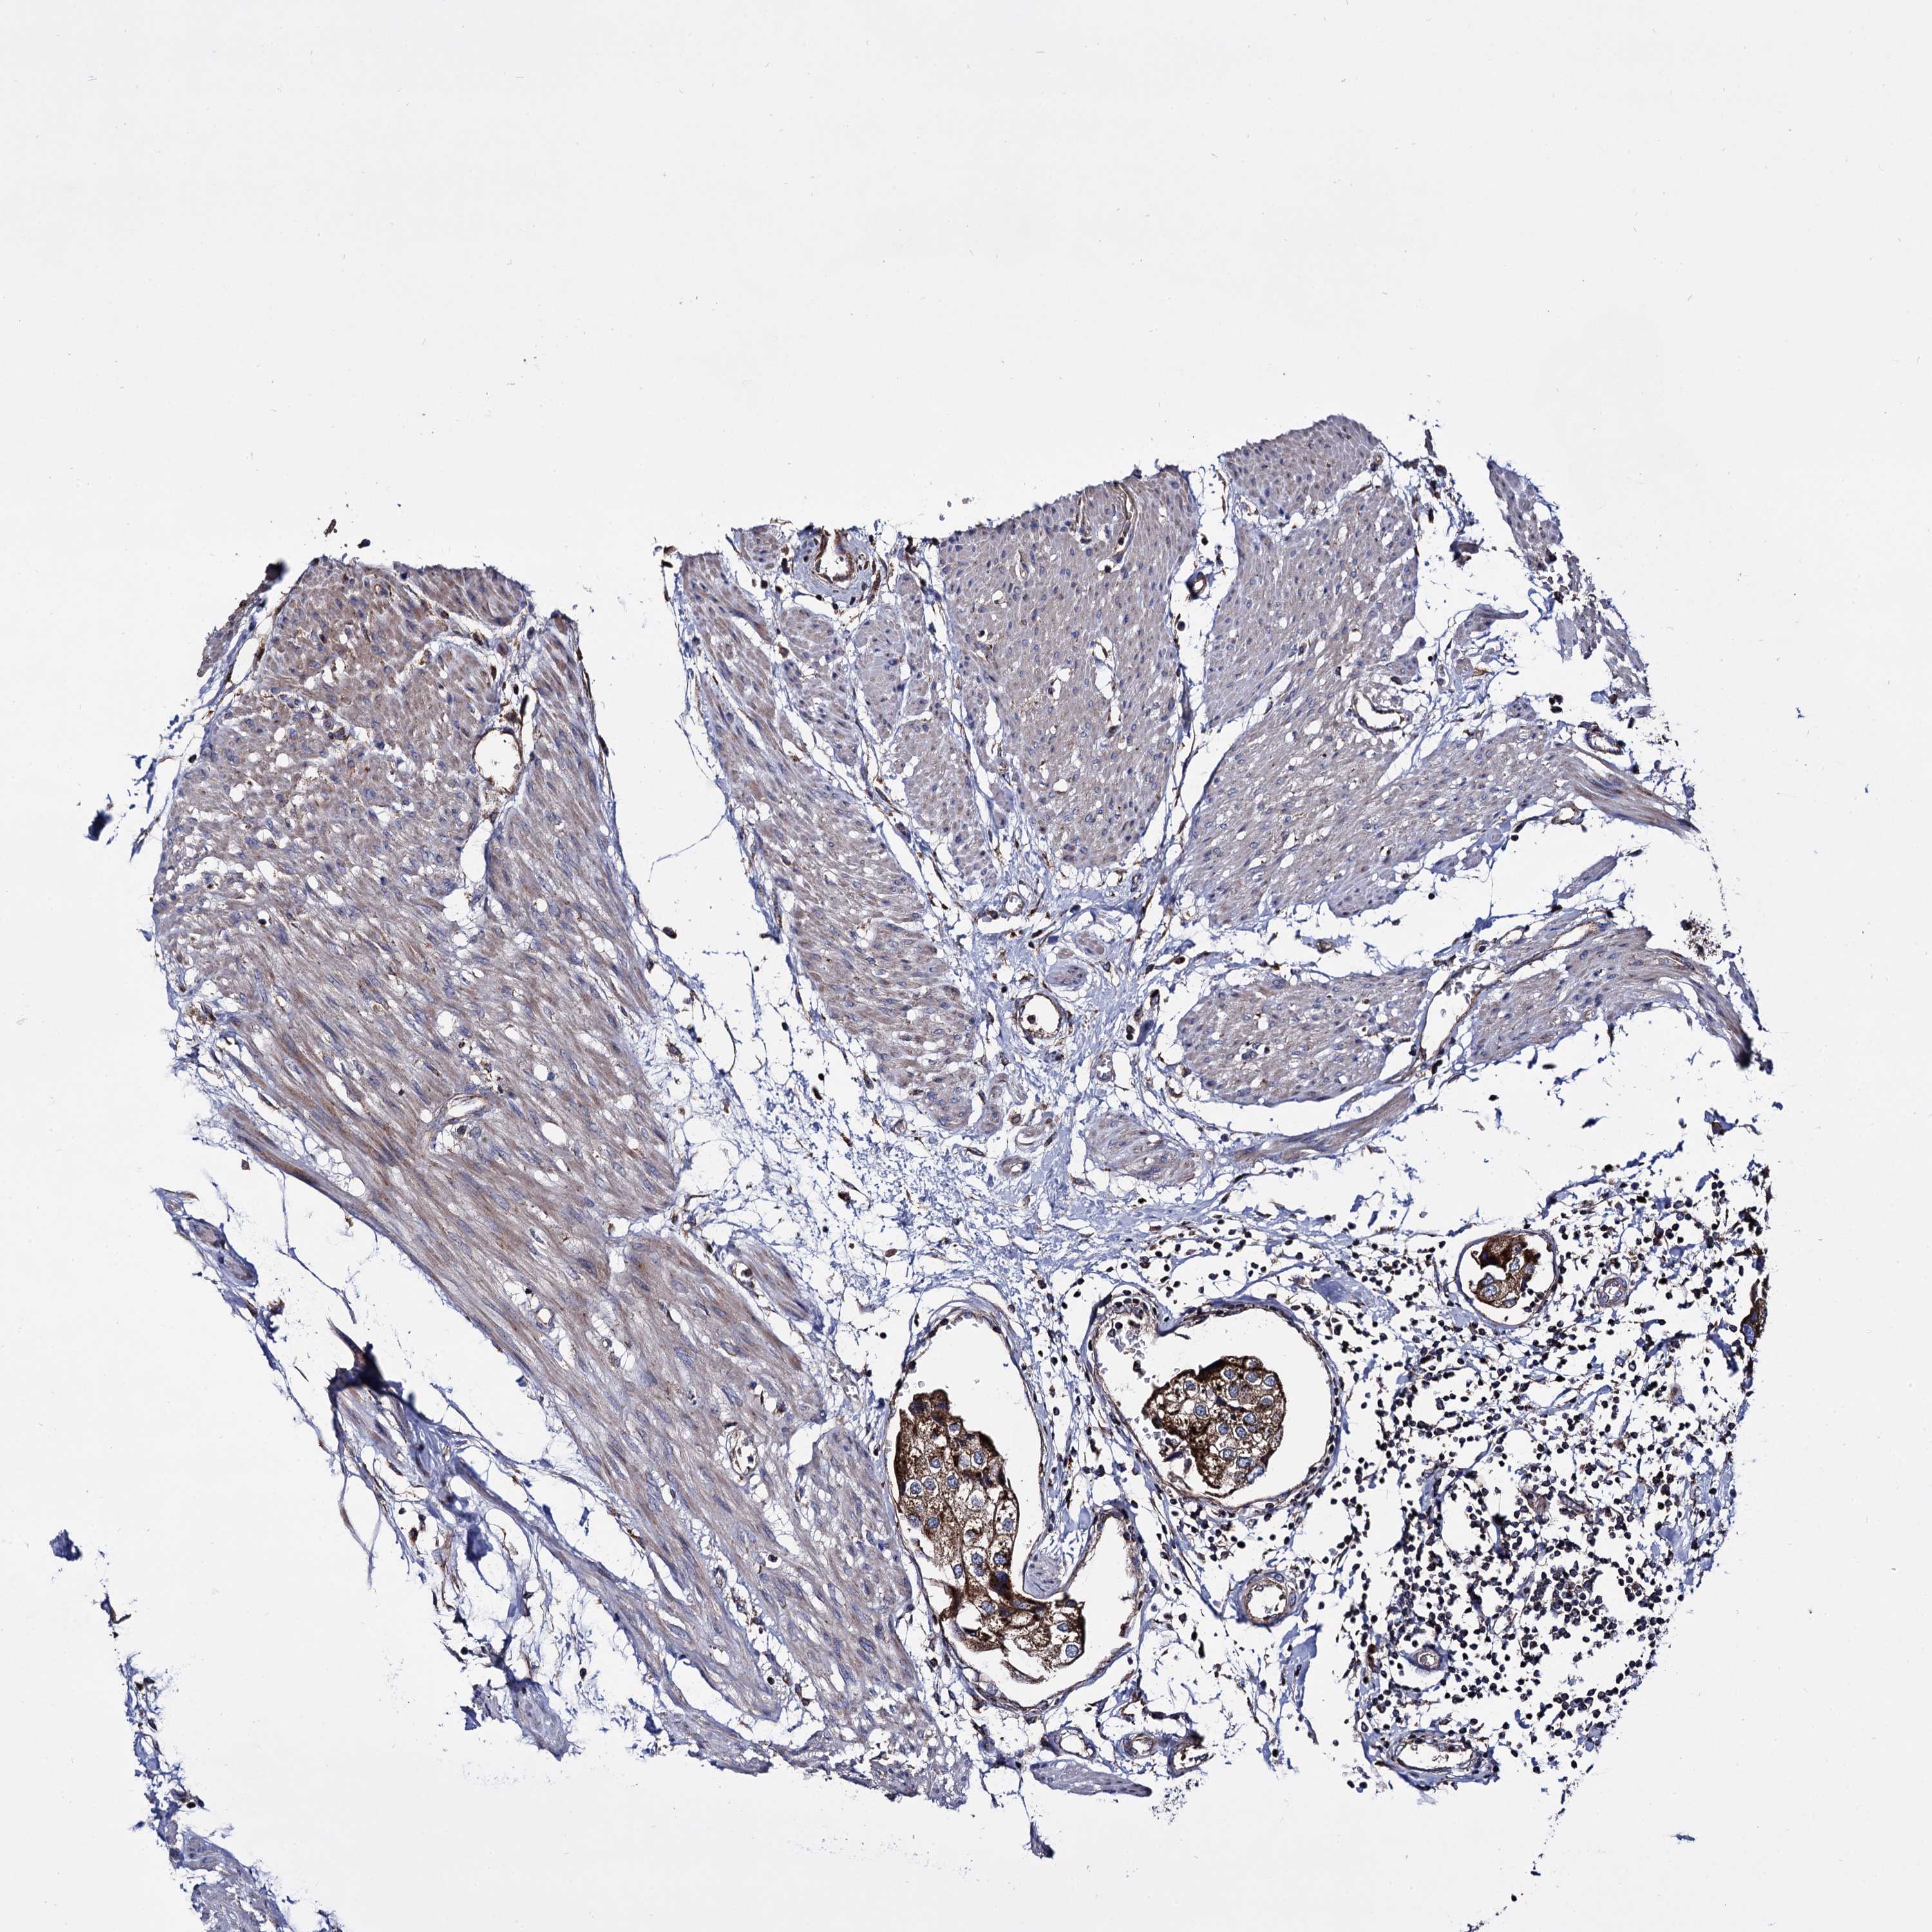

UROTHELIAL CANCER - Protein expressioni

A mouse-over function shows sample information and annotation data. Click on an image to view it in a full screen mode. Samples can be filtered based on level of antibody staining by selecting one or several of the following categories: high, medium, low and not detected. The assay and annotation is described here.

Note that samples used for immunohistochemistry by the Human Protein Atlas do not correspond to samples in the TCGA dataset.

Antibody stainingi

Antibody staining in the annotated cell types in the current human tissue is reported as not detected, low, medium, or high, based on conventional immunohistochemistry profiling in selected tissues. This score is based on the combination of the staining intensity and fraction of stained cells.

Each image is clickable and will lead to virtual microscopy that enables deeper exploration of all samples and also displays staining intensity scores, fraction scores and subcellular localization as well as patient and tissue information for each sample.

Antibody HPA040845

Staining

High

Medium

Low

Not detected

Intensity

Strong

Moderate

Weak

Negative

Quantity

>75%

75%-25%

<25%

None

Location

Nuclear

Cytoplasmic/membranous

Cytoplasmic/membranous,nuclear

Urothelial carcinoma, NOS